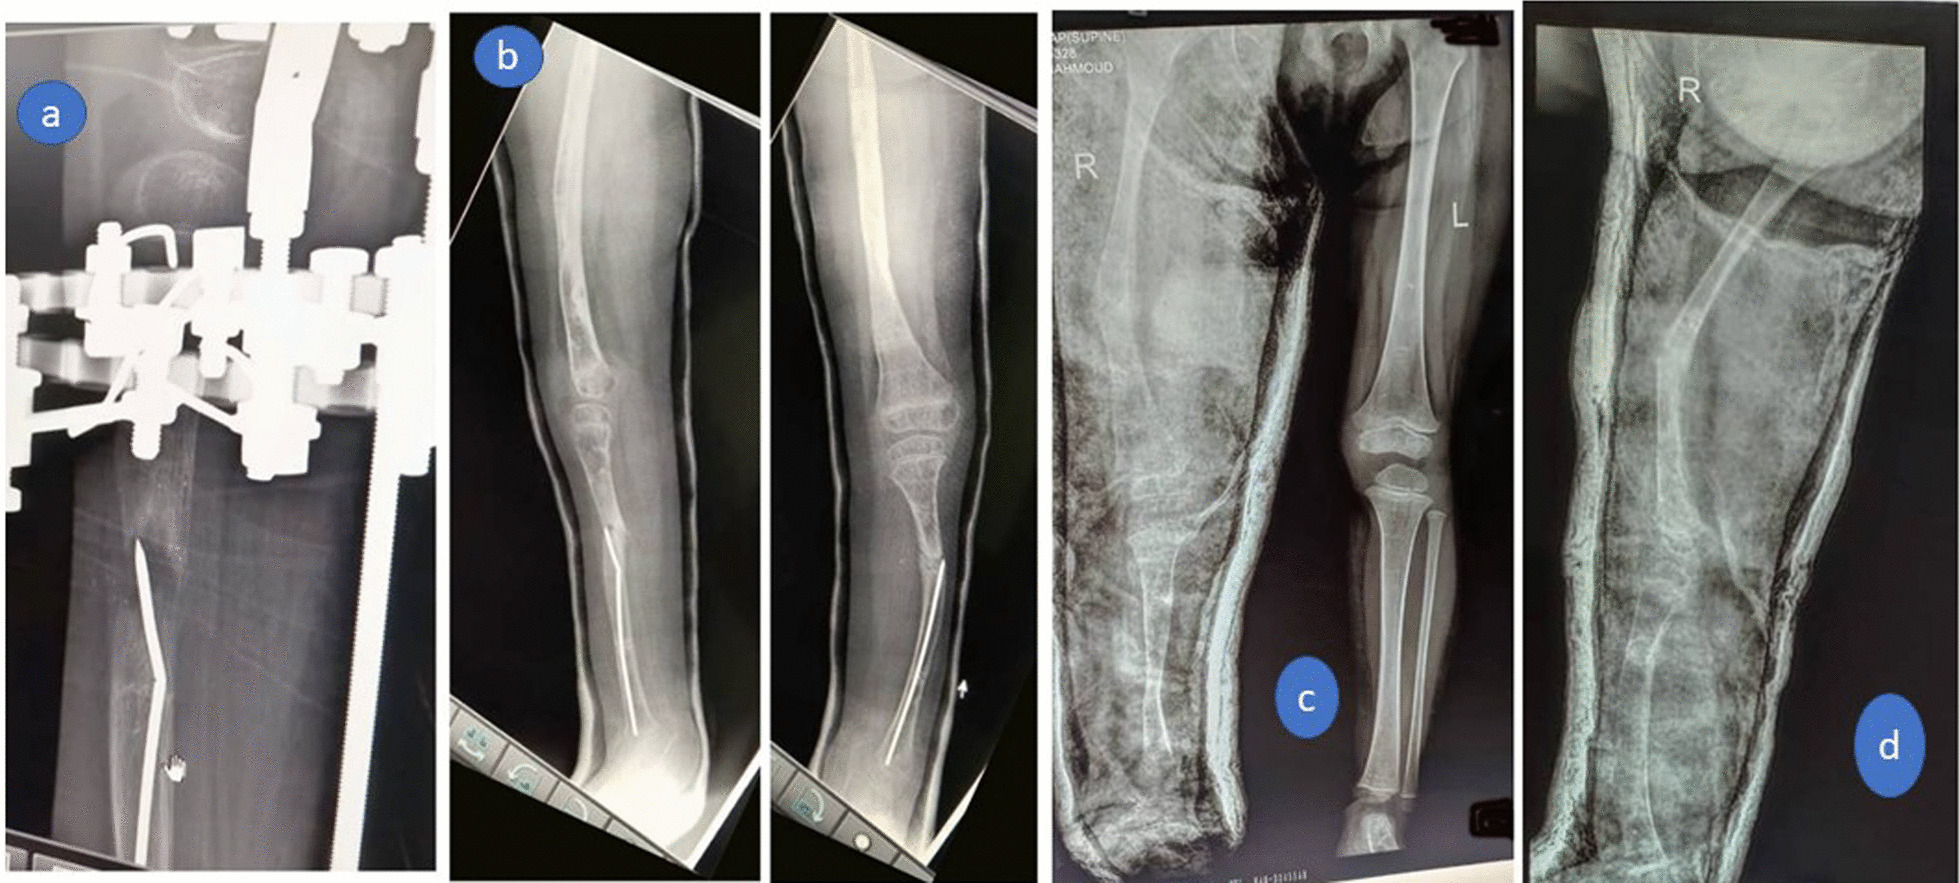

Pin tract infection occurred in all cases and was resolved with pin-site care and antibiotic treatment. No case required debridement. Knee stiffness occurred in all cases, intensive physiotherapy was performed after brace removal and full range of knee motion was regained at the time of final follow-up. No residual joint stiffness, subluxation, or dislocation occurred in any case. Superficial skin necrosis occurred in only one case (8%) at the site of the foot skin incision and was resolved by daily dressing. In two (17%) cases, valgus deformity occurred at the tibial regenerate, managed by corrective osteotomy and intramedullary rodding (Fig. 6a,b). This resulted in residual LLD of 2 cm, which could be tolerated (non-significant). Insufficiency femoral fracture at a site of previous pin happened in one case which could be treated conservatively by applying above knee cast for 1 month. (Fig. 6c, d) No complications were encountered, e.g., neurovascular injuries, compartment syndrome, knee dislocation, significant residual LLD, or regenerate fracture.

Fig. 6.

a Valgus deformity occurred at the tibial regenerate, which was managed by b corrective osteotomy and intramedullary rodding, c anteroposterior, and d) lateral x-ray images of Insufficiency fracture of the femur at the site of a previous pin